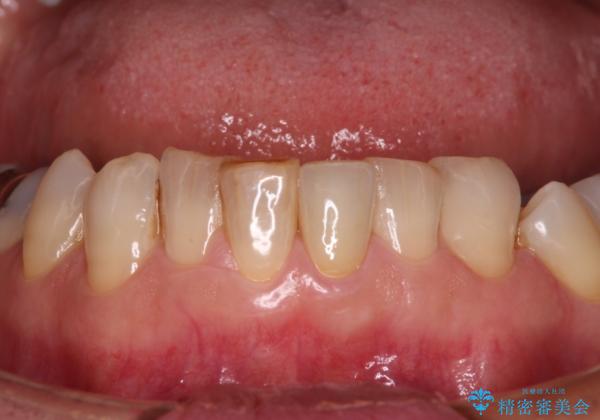

- 下顎前歯が痛んで近医を受診したところ、下顎前歯2本を抜歯してインプラント治療が必要と診断されたとのことで来院された患者様です。

診査の結果、下顎左側中切歯の神経が失活していることが痛みの原因であり、根管治療を行う必要があると診断されました。

根管治療を行った後にオールセラミッククラウンにて補綴することとしました。

隣在歯にも根尖部の炎症が及んでいるように見えましたが、術前診査では神経が失活している様子がなかったため、まずは原因歯から処置を行うこととしました。

初回の根管治療後には痛みが速やかに改善し、6か月後のレントゲン写真では根尖の病変が消失していることが確認できました。